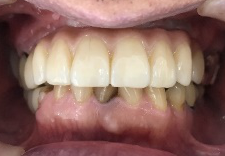

After